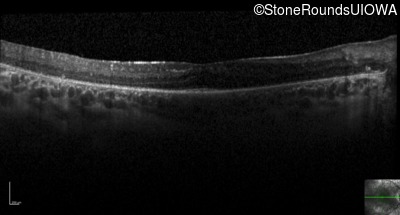

Optical Coherence Tomography - Right - 20/40 -1 sc

Exemplar / OCT Stack

OCT Stack

Optical Coherence Tomography - Left - 20/32 sc